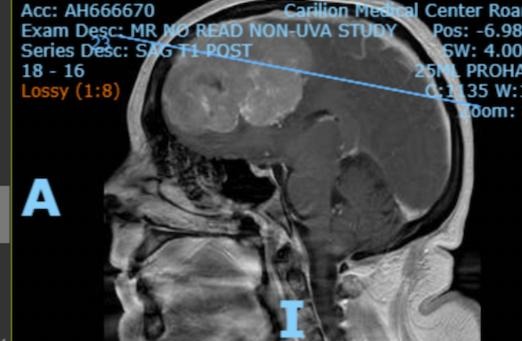

After undergoing an MRV of my brain on 08/14/2025, my neurooncologist called me on Monday, 08/18/2025 and informed me that I have another small brain tumor that is pressing up against the superior sagittal sinus vein in my brain, a large vein that drains blood and cerebrospinal fluid and helps to prevent hemorrhage and stroke, and that I must watch my stress since the MRV showed the tumor is severely constricting the vein.. as I could easily have a stroke or hemorrhage. Unfortunately she told me that the tumor is not operable as it is too risky to remove a tumor that is attached to such a large vein as it would likely cause a fatal brain hemorrhage during surgery. She is particularly concerned about the tumor growing and causing serious life-threatening issues because the large tumor I had removed was very aggressive and atypical, grade 2-3. She additionally informed me that I have yet another brain tumor discovered in the posterior (back) part of my brain that is also inoperable if it grows and starts to cause me further problems. I will continue having brain MRIs every 6 months to check for tumor growth.

She is referring me to a cancer geneticist as the largest brain tumor that was removed in 10/2024 tested positive for a very rare genetic disorder called NF2 Q410, (neurofibromatosis type 2) which causes brain and spinal cord tumors. My 24-year-old son will be undergoing testing for this genetic condition soon also. Please pray he is negative. The genetic test will see if the NF2 was confined to the resected tumor or if I indeed have the genetic disorder.

My name is Christine. Please bear with me as I try to give an abbreviated version of a long story. I underwent two urgent brain surgeries, six days apart, approximately five months ago, to remove a massive 8.5 cm cancerous brain tumor. I spent two weeks in the ICU and 31 days in the hospital in Roanoke, VA. After the first brain surgery, I was told I had a blood clot on the top of my brain, for which I am continuing daily medication. It is called a CVST, which is a rare stroke. .. five days after my first surgery I was told I would need a second brain surgery because there was still some of the tumor left that needed to be removed.

I will need to undergo brain MRIs for the rest of my life to check for regrowth because the mass was aggressive and malignant, as there is a high probability of regrowth on my brain and/or spinal cord. I have been recovering from the surgeries at my sisters for the past 4 months and have been recently released to go back to work, hence I’ve been applying for several jobs. I just recently completed approximately three months of physical therapy, which has been somewhat helpful for my left leg weakness/nerve damage.